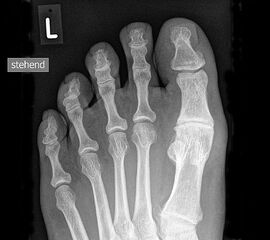

Klinisch zeigt sich stadienabhängig eine schmerzhafte Bewegungseinschränkung mit zunehmender Steifigkeit des Großzehengrundgelenkes. Vor allem die Einschränkung der Dorsalextension wird von den Patienten oft als unangenehm empfunden. Initial besteht eine bindegewebige Alteration im Gelenk, im weiteren Stadium treten Knorpeldegeneration und Begleitsynovialitis mit der Ausbildung von osteophytären Randanbauten auf. Klinische treten diese meist durch eine schmerzhafte dorsale Knochenkante in Erscheinung (Abbildung 1).

Im späten Stadium imponiert eine Gelenkblockierung durch freie Gelenkkörper. Während in den Anfangsstadien vor allem die dorsalen Anteile des Gelenks betroffen sind, betreffen die Veränderungen in den Fortgeschrittenen Stadien die gesamte Zirkumferenz einschließlich des Sesambeingleitlagers. Im Endstadium kommt es zu einer weitgehenden Ankylosierung des 1. Metatarsophalangealgelenks.

• Röntgenaufnahme des Fußes in drei Ebenen unter Belastung